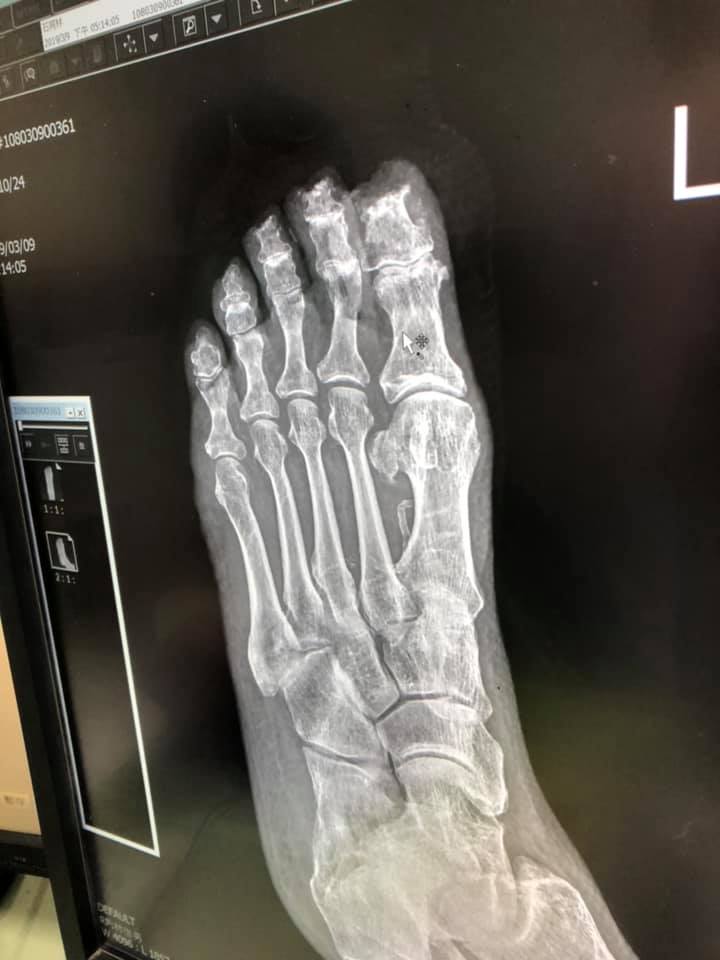

▼當時移工還沒有發現不對勁,一直到有路人看到情況後馬上跟原po的奶奶說,爺爺才被馬上送醫。照了X光後醫生表示連骨頭也被磨掉了一些,這樣的狀況讓原po忍不住大罵「到底要怎樣才能弄成這樣,垃圾!」